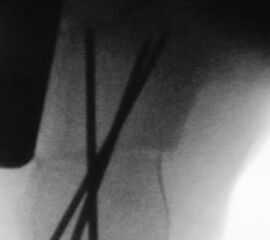

Zusätzlich schränken Wachstumsfugen die Wahl der Osteosynthese ein. Eine die Fuge kreuzende Osteosynthese ist ausschließlich mit Kirschner-Drähten möglich (Abb. 3).

Abb. 3 a-j: Beispiel einer Calcaneusverschiebeosteotomie mit offenen Wachstumsfugen und der entsprechenden Osteosynthese mit Kirschner Drähten. Lokalisation der Osteotomie (a), Lage der Fräse (b-d), Drahtlage mehrere Ansichten (e-h), Heilung der Osteotomie 4 Wochen postoperativ und Entfernung der Drähte (i-j).

Zum Lesen der Bildbeschreibung und zur Vollansicht bitte die Bilder anklicken. Bilder: A. Helmers.